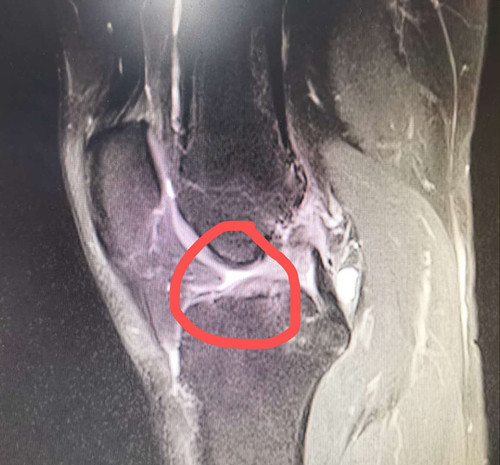

2年前的一场足球友谊赛,对热爱运动的人民警察黄先生来说,是个痛苦的记忆。在那场球赛中他一个高速转身动作,右膝关节扭了一下。紧接着,他感觉一股剧痛从右膝关节传来,整个膝关...